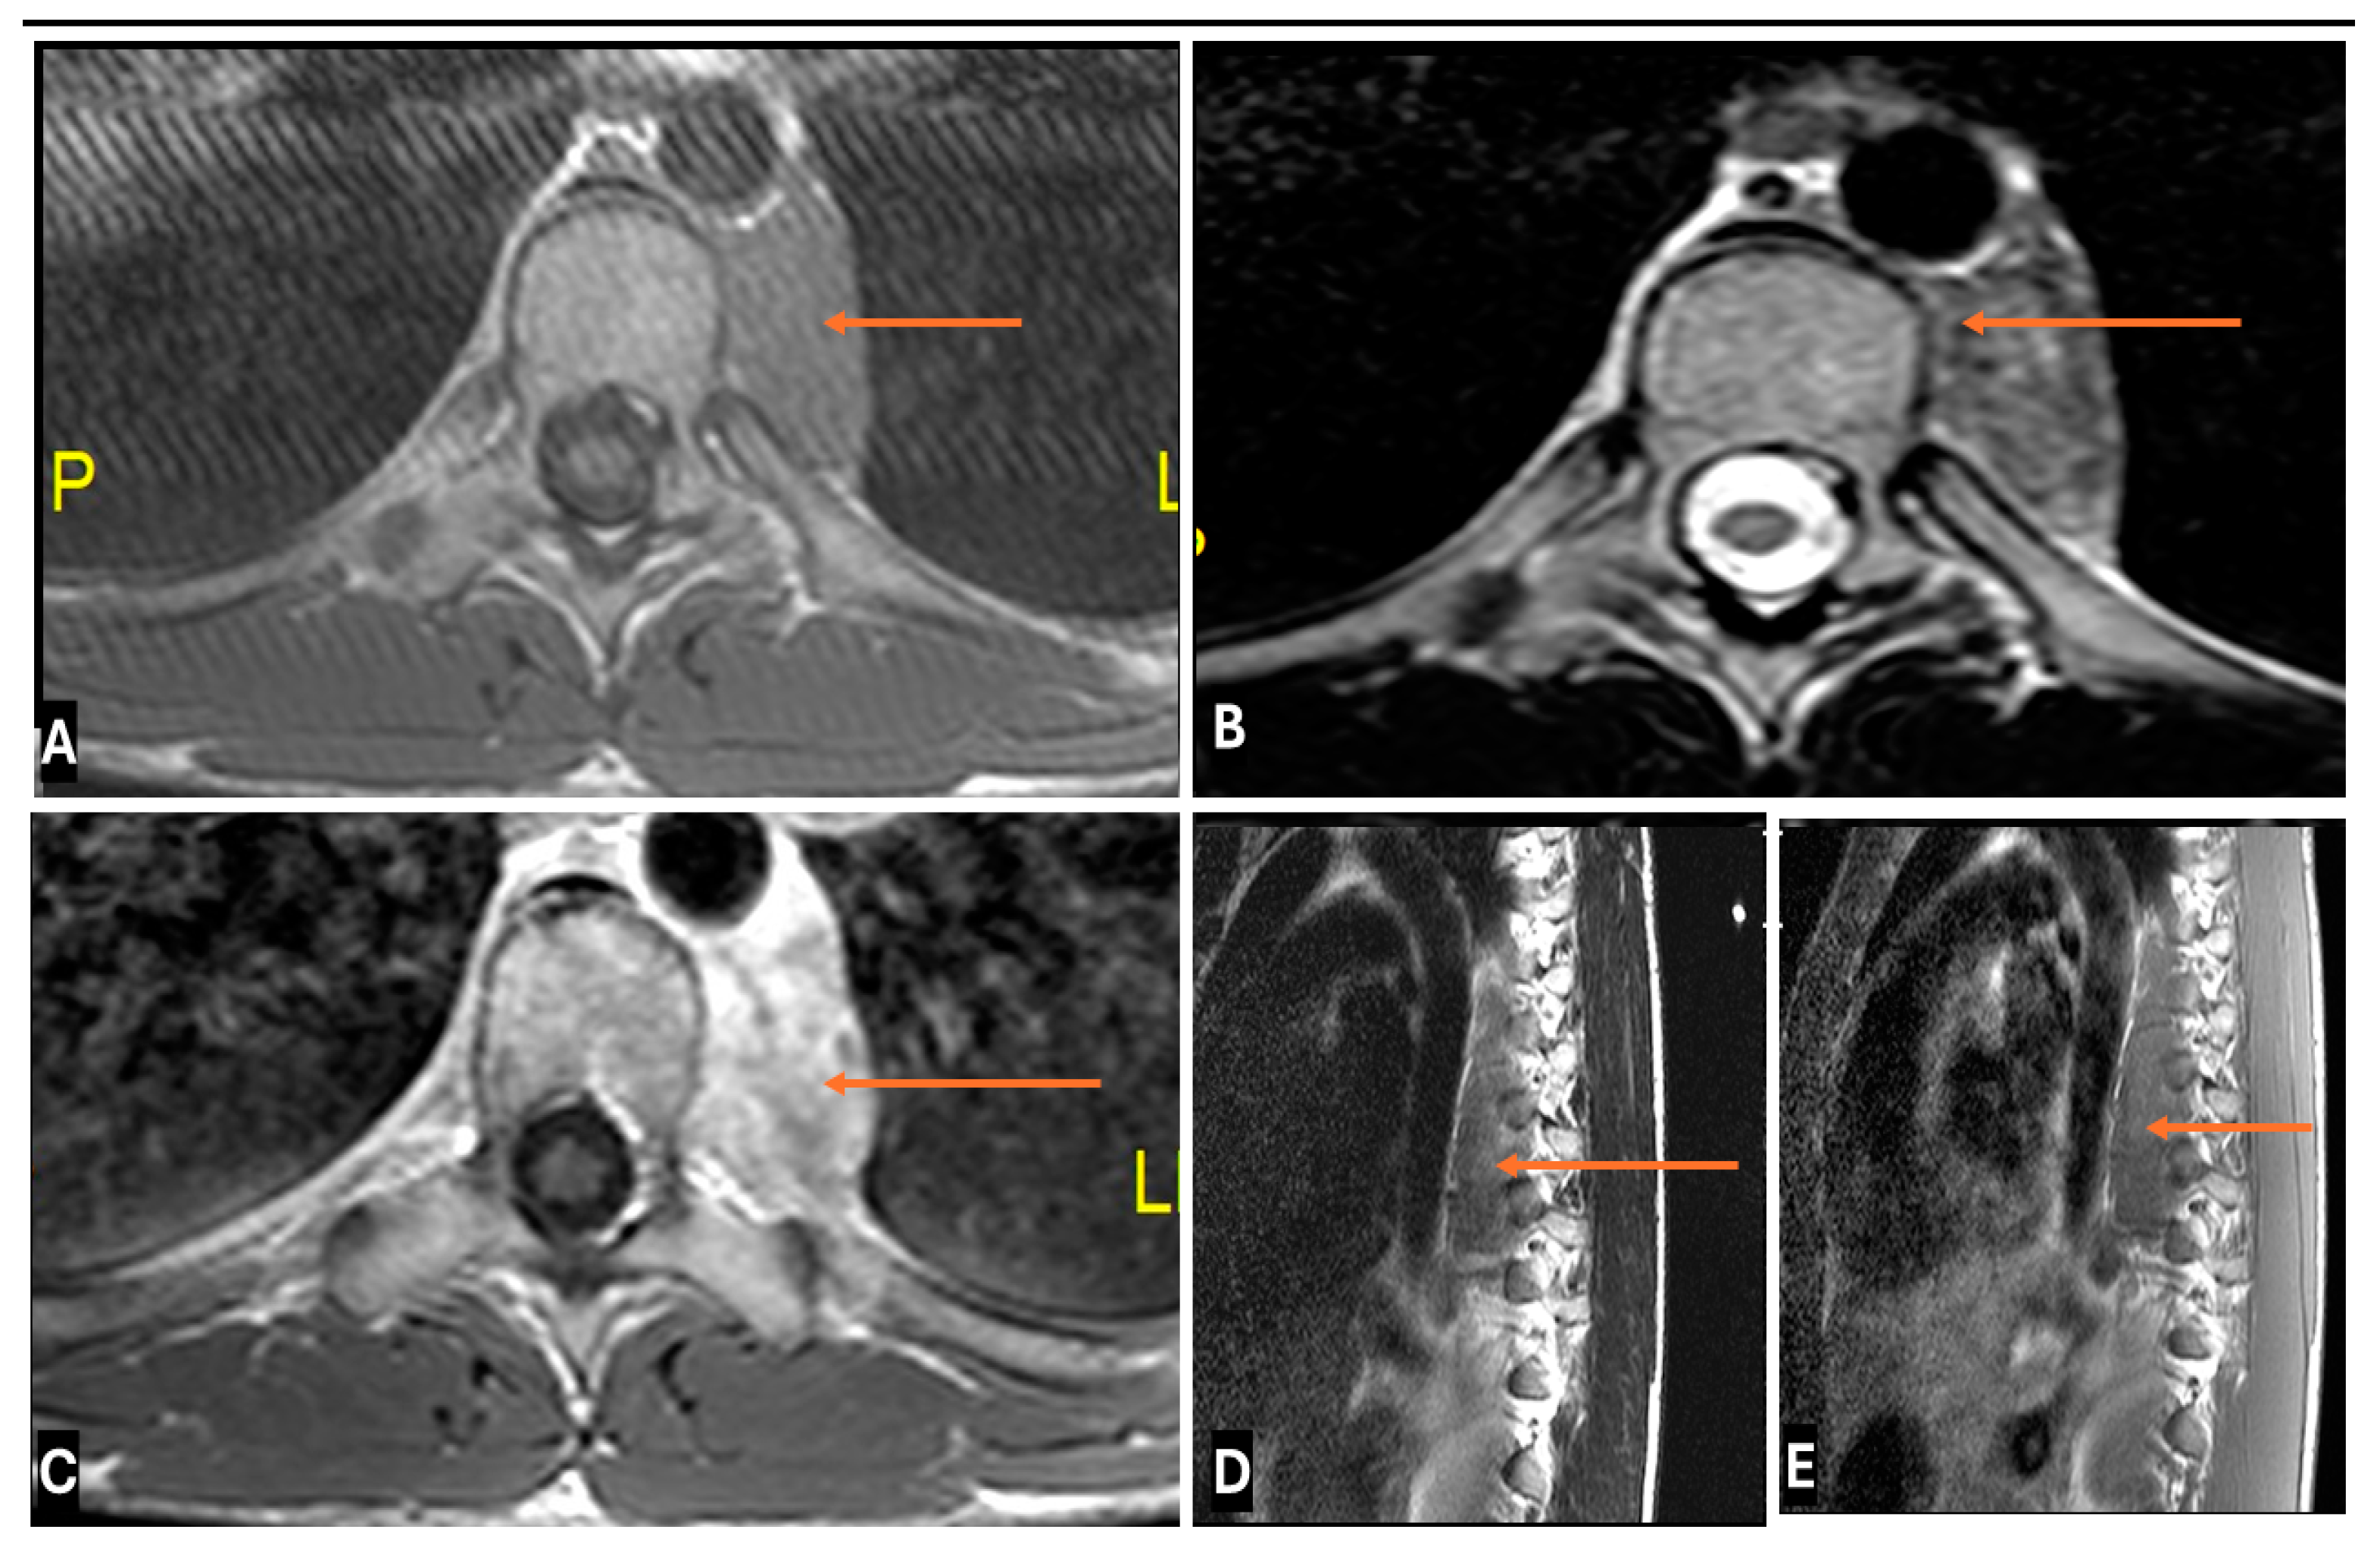

- Neurolymphomatosis describes intraneural spread of lymphoma and appears as diffuse enlargement of nerves, plexuses, spinal cord, and cauda equina. It shows more homogeneous enhancement than PNSTs and may be associated with lymphadenopathy or a known history of lymphoma [63] (Figure 20 and Figure 21).